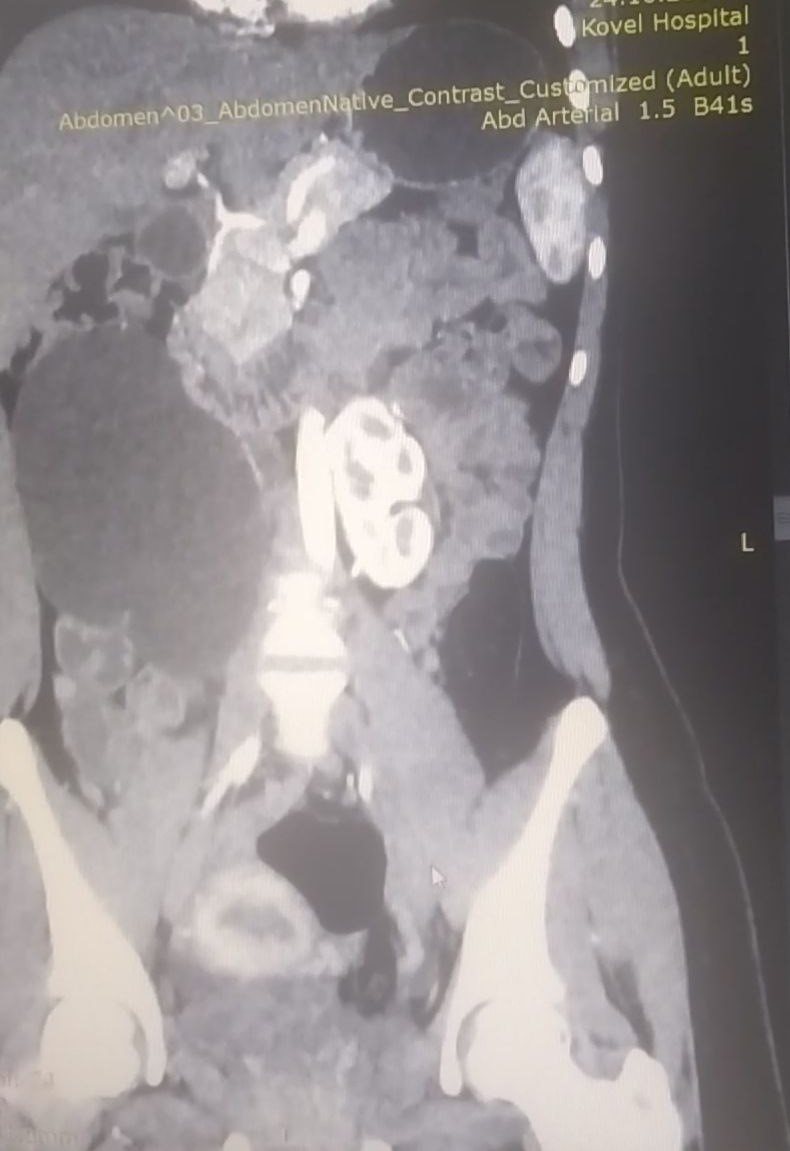

17-річна пацієнтка мала вроджену ваду сечовидільної системи - підковоподібну нирку (зрощення двох нирок). Стан її здоров’я погіршувався упродовж багатьох років, аж поки права половина підковоподібної нирки перестала функціонувати.

Хвору доставили в лікарню у важкому стані з вираженим больовим синдромом та наявністю гіпертонічного кризу. Через звуження у сечоводі та ускладнення відтоку сечі, об’єм рідини в нирці сягнув критичного рівня. А збільшення її розмірів стало помітним навіть зовні.

Лікарі діагностували термінальний гідронефроз із наслідками, гідронефротичну трансформацію правої половини підковоподібної нирки, вторинну артеріальну гіпертензію.